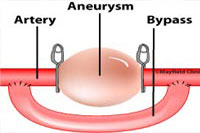

El Dr. Mura explica que los aneurismas son dilataciones arteriales circunscritas que se producen por debilidad de su pared, de manera que se inflan como un pequeño globo, con el riesgo de que revienten o sangren. Los tratamientos habituales son mediante una intervención que inserta un clip metálico que cierra el aneurisma o su "relleno" mediante la inserción de un catéter endovascular, lo que podría ser a través de una pierna, por ejemplo.

"Pero existen casos en que ninguna de esas dos posibilidades es viable, debido a que el flujo de sangre a través de las arterias está incluido en el problema, de modo que ahí es cuando es necesario hacer bypass cerebrales", añade el doctor Mura.

La gran mayoría de las veces los bypass son extra intra craneales; es decir, con una arteria de fuera de la zona afectada, "generalmente la llamada "temporal superficial", -que es la que uno siente en las sienes cuando duele la cabeza-, se lleva desde fuera del canal sangre hacia adentro, resecando primero la que tiene el aneurisma", explica.

Pero en el caso de los bypass intra intra craneales, se usa un trocito de la misma arteria temporal superficial y se pone en la arteria con aneurisma, haciendo un desvío que rodea la zona afectada, que antes se ha resecado con dos clip metálico.